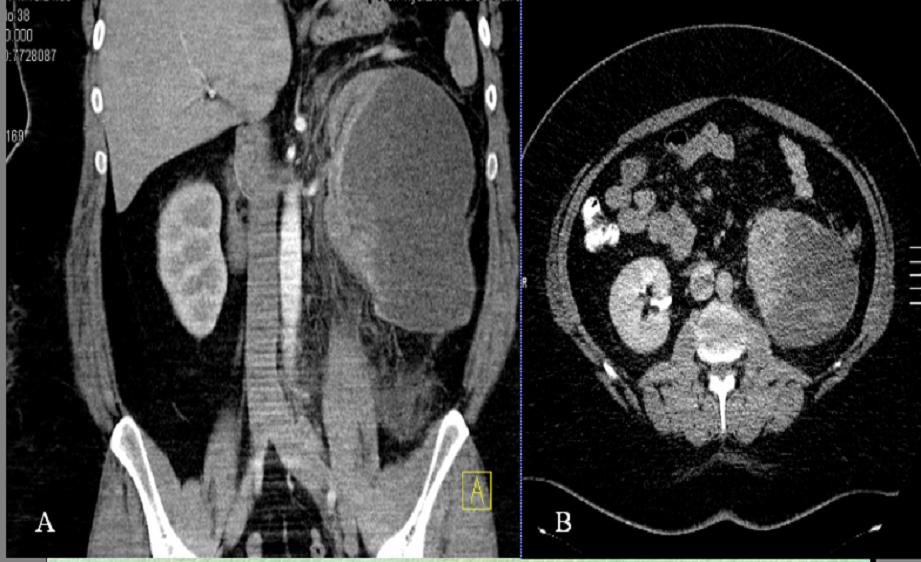

Los tumores neuroectodérmicos primitivos de origen renal (rPNET) son neoplasias excepcionales y pertenecen al grupo de tumores neuroectodérmicos periféricos malignos. Son tumores extremadamente agresivos, con tendencia a la recurrencia y a la metastatización temprana. Esta entidad pueden ser confundida con toda la variedad de tumores de células redondeadas de pequeño tamaño. De manera que es importante hacer el diagnóstico diferencial con ellas por sus implicaciones terapéuticas y pronósticas.Descargas